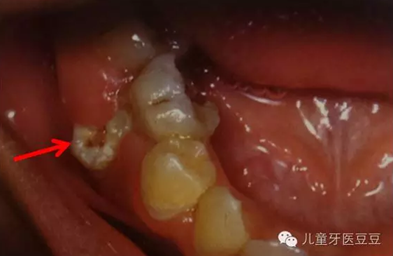

0IG~(~2ELPN~$0HI(Q[)2$6.png

乳牙反復(fù)根尖發(fā)炎導(dǎo)致繼承恒牙發(fā)育不良